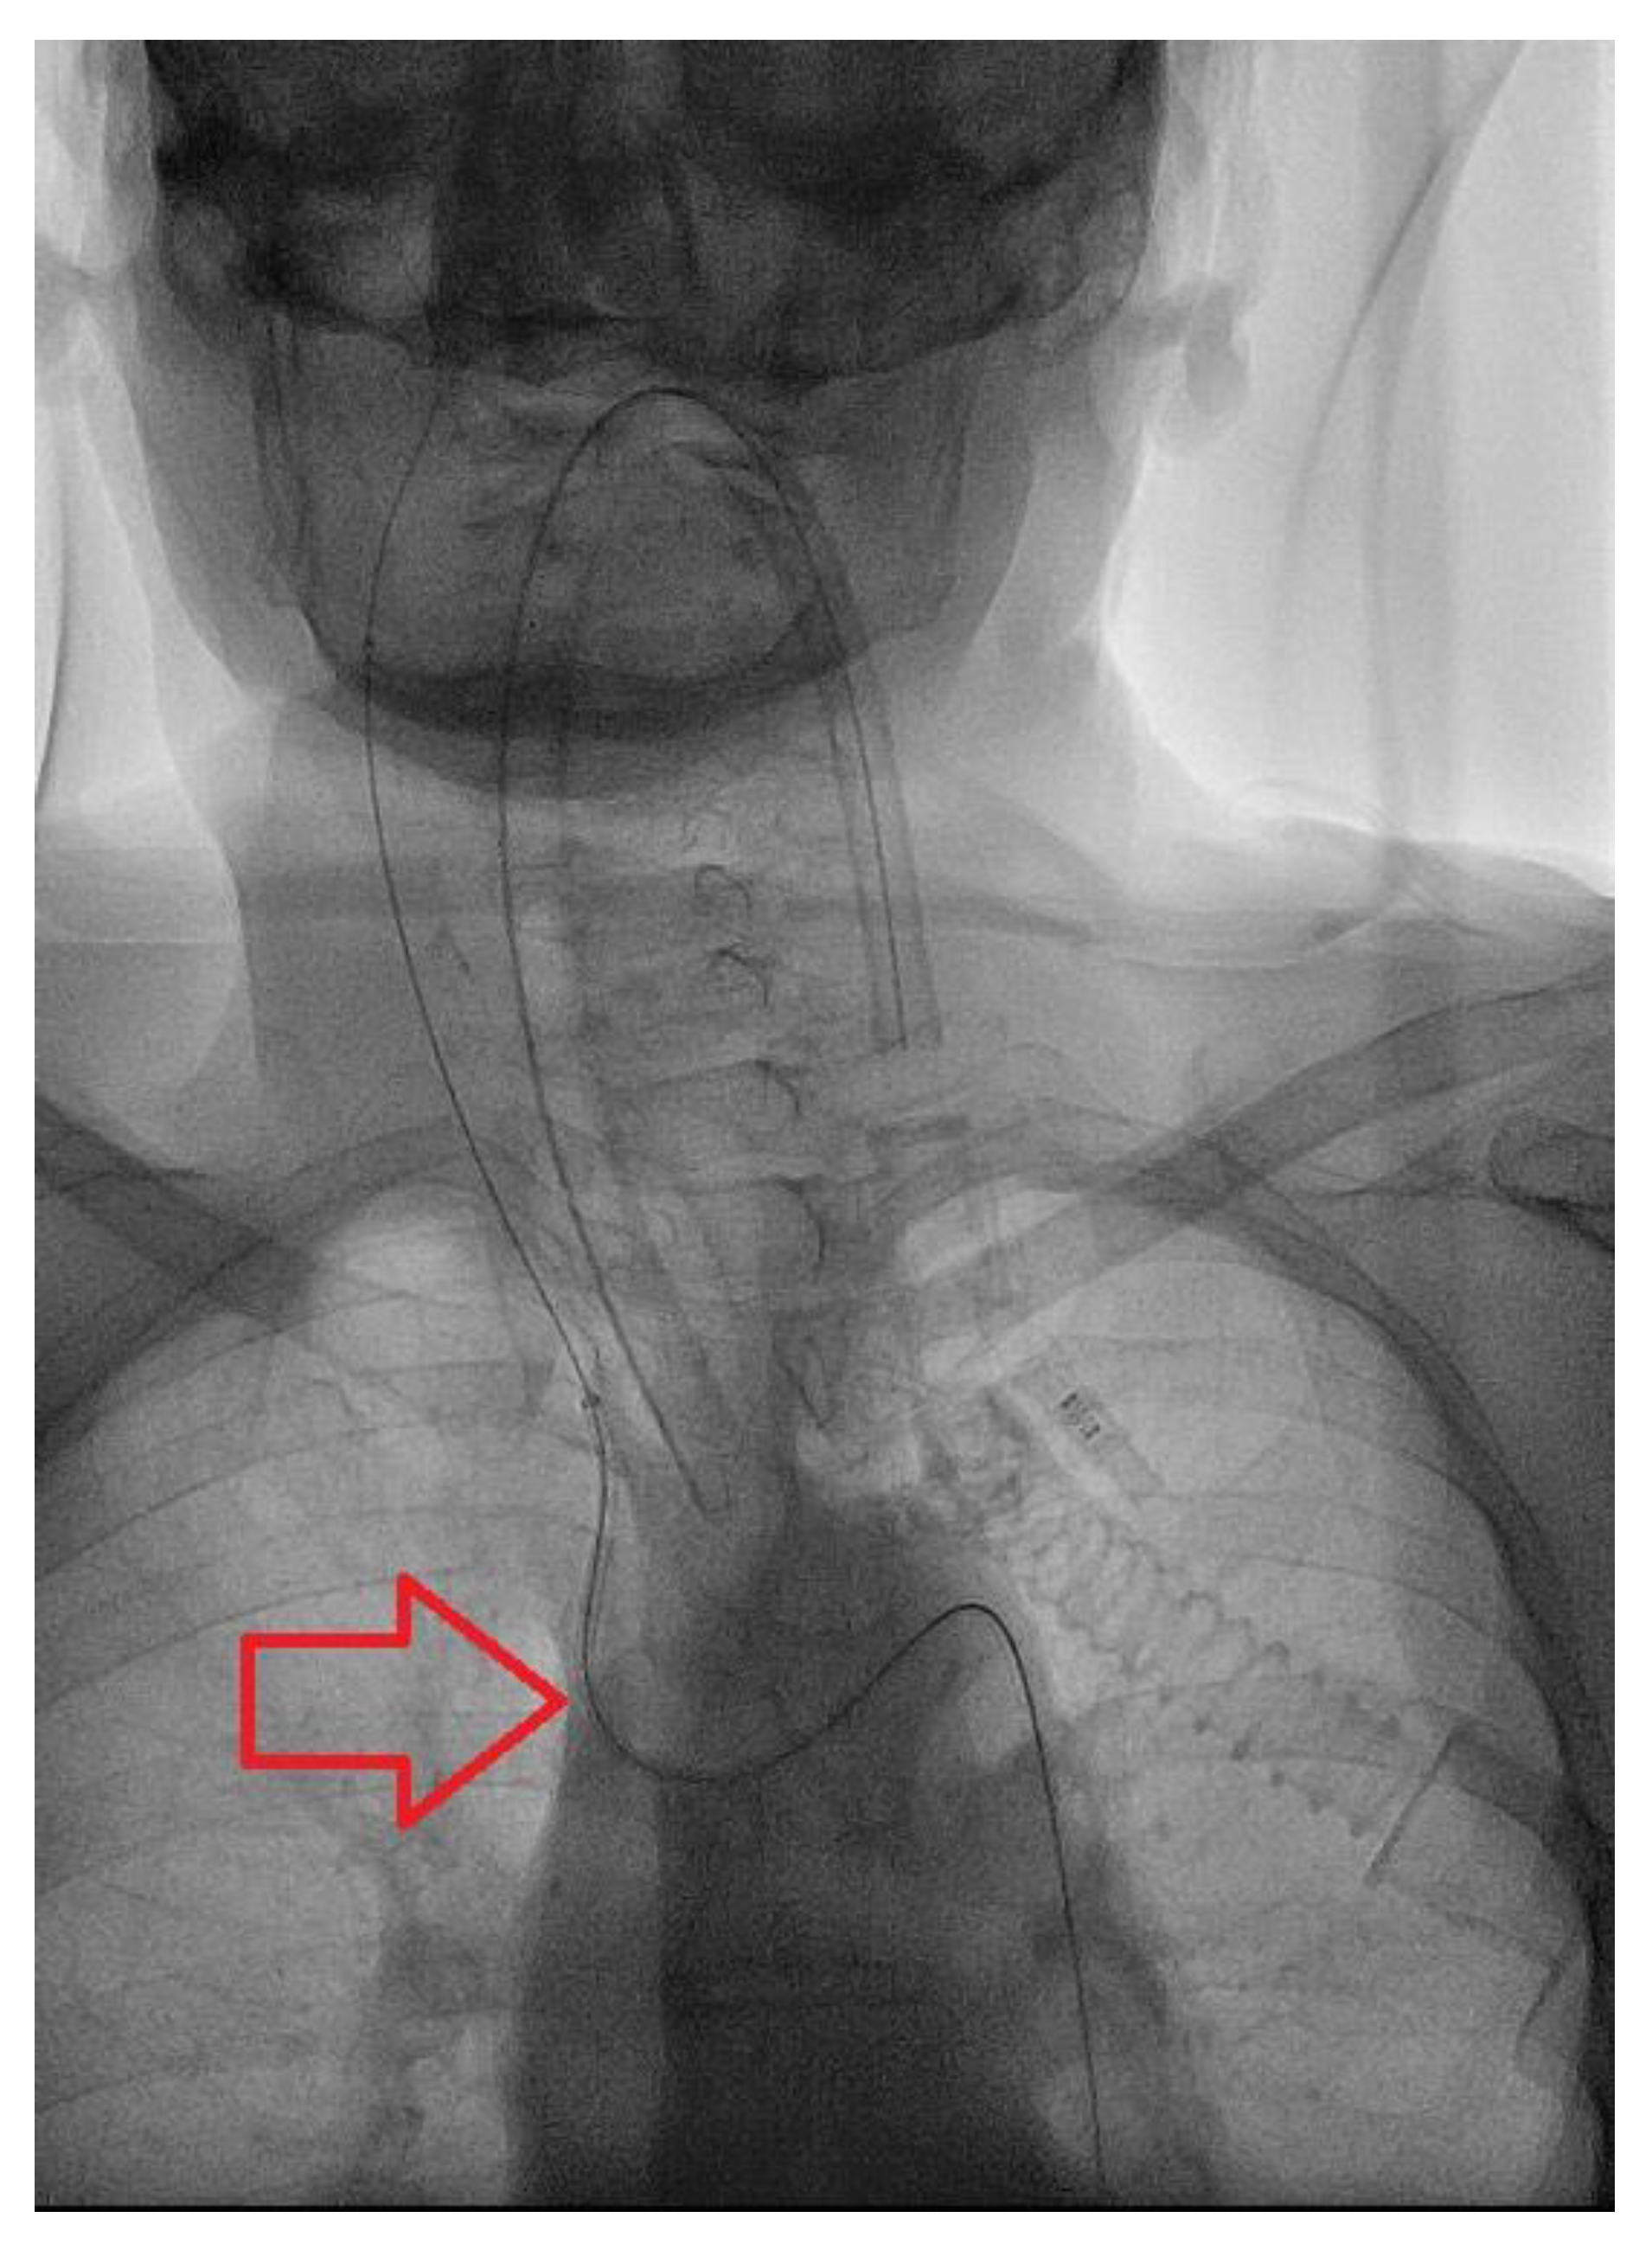

2. Case Presentation